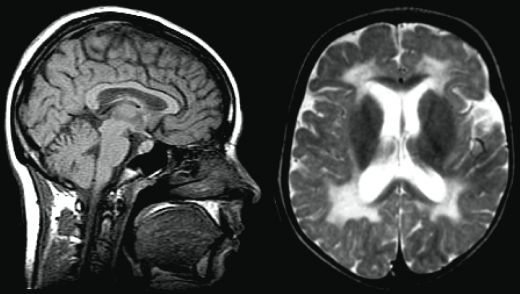

Beyin emarı, manyetik rezonans görüntüleme (MRG) teknolojisi ile beyin dokusunun ayrıntılı görüntülerinin elde edilmesini sağlar. Nörolojik hastalıkların tanısı ve tedavi süreçlerinde kritik bir rol oynar. Bu yöntem, non-invazif yapısı ve yüksek çözünürlüğü ile öne çıkar.

Beyin Emarı Nedir?Beyin emarı, manyetik rezonans görüntüleme (MRG) teknolojisi kullanılarak beyin dokusunun detaylı görüntülerinin elde edilmesini sağlayan bir tıbbi görüntüleme yöntemidir. Bu yöntem, beyin hastalıklarının teşhisinde, tedavi planlamasında ve hastalıkların izlenmesinde kritik bir rol oynamaktadır. Beyin Emarının Tarihçesi Manyetik rezonans görüntüleme tekniği, 1970'lerin sonlarına doğru geliştirilmiştir. İlk beyin emarı görüntüleri, 1980'lerde elde edilmeye başlanmış ve bu teknoloji hızla yaygınlaşmıştır. Zamanla, beyin emarı, nörolojik hastalıkların tanısında standart bir yöntem haline gelmiştir. Beyin Emarının Çalışma Prensibi Beyin emarı, güçlü bir manyetik alan ve radyo dalgaları kullanarak çalışır. Bu işlem sırasında, hastanın vücudundaki protonlar manyetik alan tarafından hizalanır. Radyo dalgaları uygulandığında, protonlar enerjilerini serbest bırakır ve bu enerjinin ölçülmesiyle beyin dokusunun detaylı görüntüleri elde edilir. Beyin Emarının Kullanım Alanları Beyin emarının birçok önemli kullanımı bulunmaktadır:

Beyin emarı, yani manyetik rezonans görüntüleme (MRG), genellikle hastanede oldukça konforlu bir ortamda gerçekleştirilir. İşlem öncesinde hastanın durumu hakkında bilgi alınır ve gerekli hazırlıklar yapılır. Hasta, genellikle sırt üstü yatar pozisyonda, özel bir masanın üzerine yerleştirilir. MRG cihazı büyük bir mıknatıs ve radyo dalgaları kullanarak görüntüleme yapar. Cihazın gürültülü çalışması nedeniyle hastalara genellikle kulaklık verilir.

Beyin emarı, beyin sağlığı açısından kritik bir muayenedir. Bu işlem, tümörler, inme, beyindeki kanamalar ve diğer anormalliklerin tespitinde son derece etkilidir. Ayrıca, hastalara tedavi planlaması ve takip süreçlerinde önemli bilgiler sunar. Erken tanı, birçok beyin hastalığında tedavi seçeneğini artırır ve hastaların yaşam kalitesini olumlu yönde etkiler.